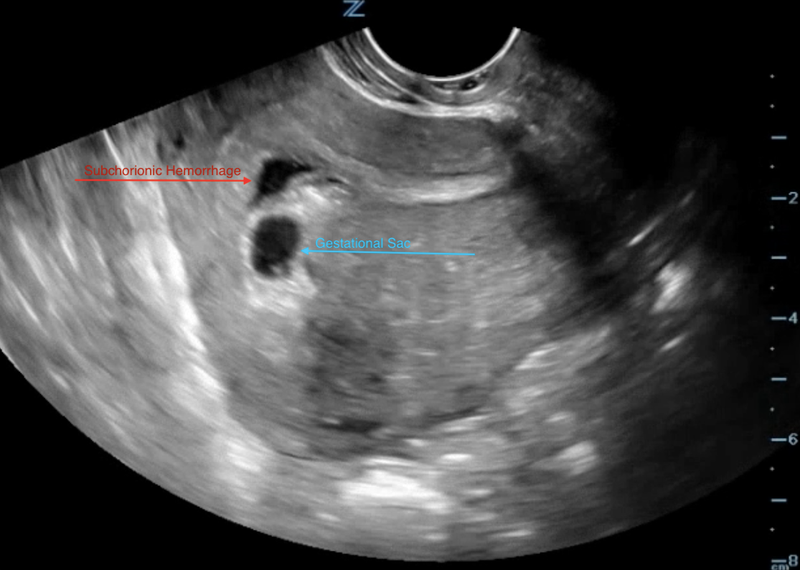

Tụ dịch màng nuôi, còn được gọi là tụ dịch sau màng đệm (subchorionic hemorrhage), là tình trạng xuất hiện dịch lỏng hoặc máu tích tụ giữa màng nuôi và tử cung. Đây là hiện tượng thường gặp trong giai đoạn đầu của thai kỳ, khi túi thai chưa phát triển hoàn chỉnh và dễ bị tổn thương. Nguyên nhân gây ra tụ dịch màng nuôi có thể do các yếu tố cơ địa, như rối loạn nội tiết tố hoặc các tác động từ bên ngoài, như chấn thương, nhiễm trùng hoặc áp lực từ tử cung. Mặc dù không phải tất cả các trường hợp tụ dịch màng nuôi đều nguy hiểm, nhưng nếu kích thước dịch tụ lớn, nó có thể gây ra những biến chứng nghiêm trọng, ảnh hưởng tới sức khỏe người mẹ và sự tăng trưởng của thai nhi.

Các bác sĩ thường sử dụng siêu âm để đo kích thước khối máu tụ và so sánh tỷ lệ này với kích thước túi thai để đánh giá mức độ nguy hiểm. Việc theo dõi và thăm khám định kỳ là rất quan trọng để phát hiện sớm và quản lý tình trạng tụ dịch màng nuôi hiệu quả. Nếu nhận thấy các triệu chứng không bình thường, bạn nên ngay lập tức liên hệ với bác sĩ để được tư vấn và điều trị kịp thời, đảm bảo an toàn cho cả mẹ và bé trong suốt thai kỳ.